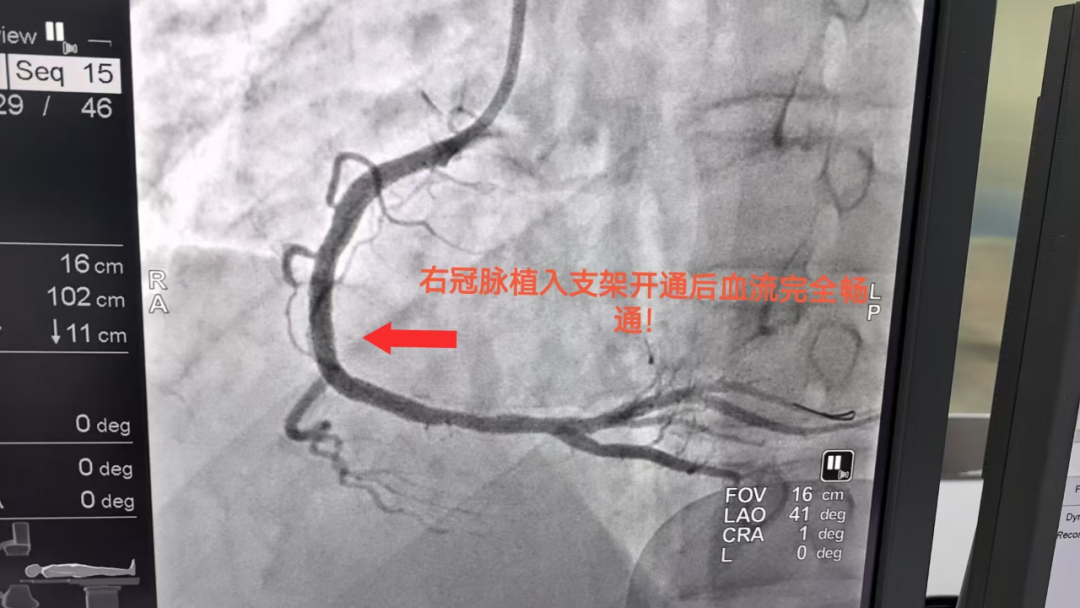

该患者入院前 1 小时因饮酒后突发胸前区剧烈疼痛、大汗淋漓,伴濒死感!胸痛持续无法缓解,我院心电图提示Ⅱ、Ⅲ、aVF 导联 ST 段明显抬高!典型的急性下壁心肌梗死,病情极凶险、随时可能危及生命,经我院 DSA 心内介入团队全力救治后成功开通梗死血管,将患者从「死神」手里抢回。

该患者从进入 DSA 导管室到成功开通血管,手术时间不超过 1 小时!手术创口仅 2 mm 大小!术后恢复良好,舒适度高,各项生命征均稳定。